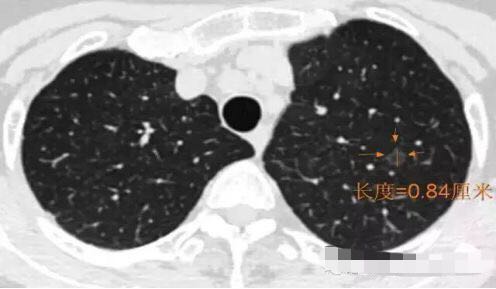

随访3年,GGO直径基本没有变化

2013年12月

2014年7月

2015年5月

2016年10月